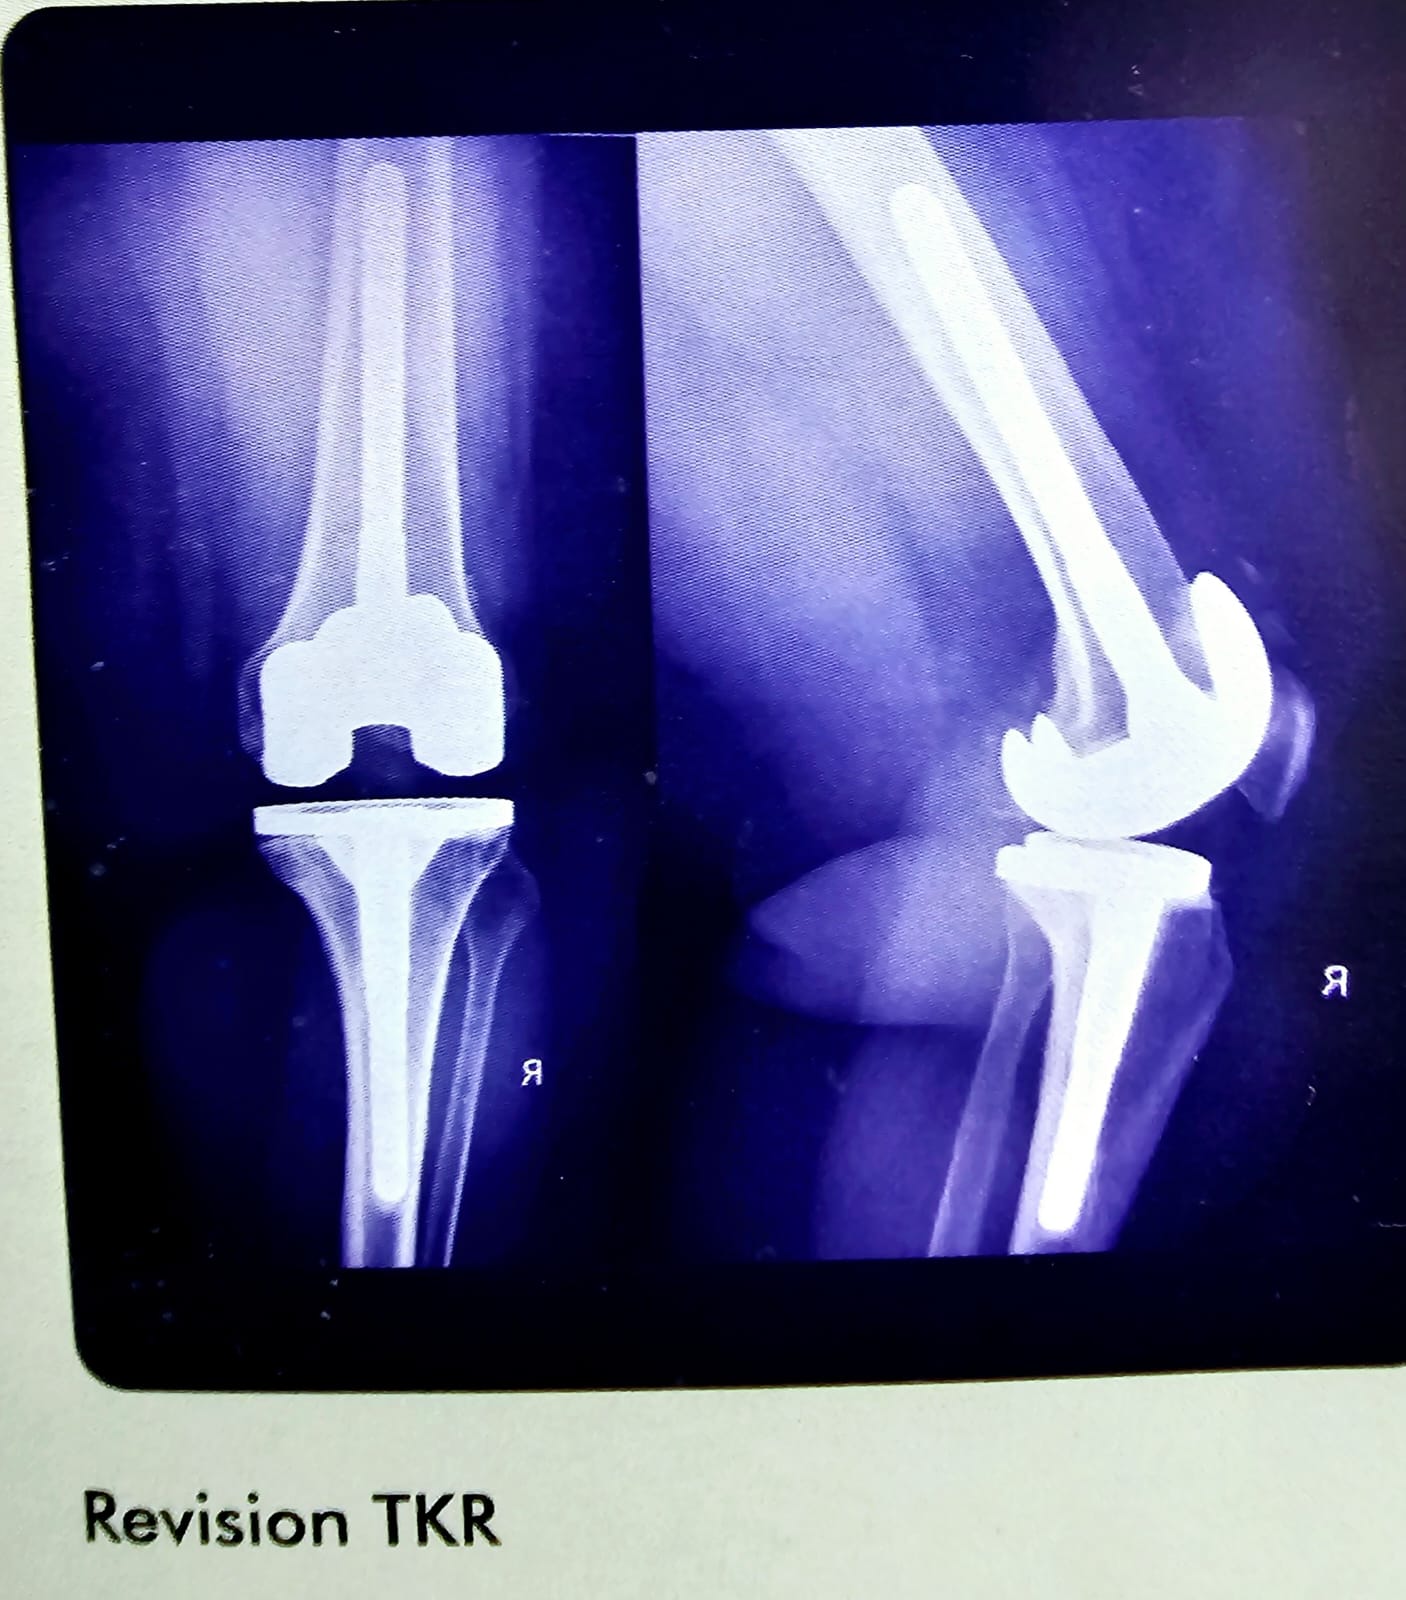

Revision TKR

This is a case of revision total knee replacement. You can see I have used both femeral and tibial stems. Stable redemption.